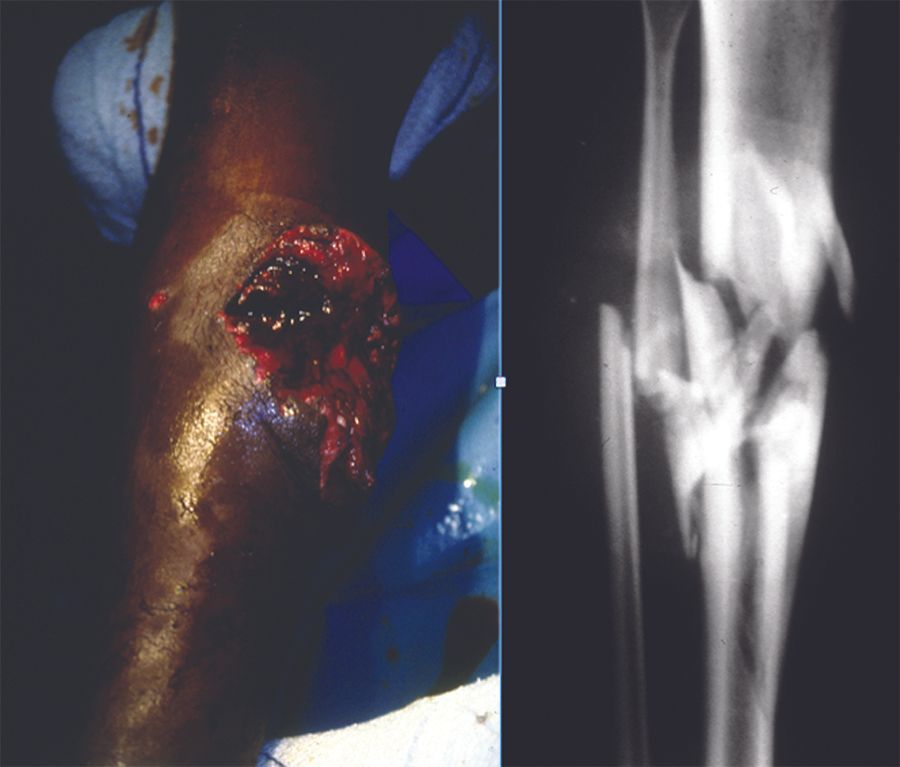

Voyage Prise en charge actuelle des traumatismes des membres en contexte de guerre. Partie 2 : Traitement chirurgical primaire et secondaire , L. Mathieu Hôpital d’Instruction des Armées Desgenettes, Lyon , Antoine Bertani Service de chirurgie orthopédique et traumatologique, Hôpital d’Instruction des Armées Desgenettes, Lyon, France , F. Rongieras Hôpital d’Instruction des Armées Desgenettes, Lyon , P. Duhamel Service de chirurgie plastique et reconstructrice, Hôpital d’Instruction des Armées Percy, Clamart , F. Chauvin Service de chirurgie orthopédique et traumatologique, Hôpital d’instruction des Armées Desgenettes, Lyon , S. Rigal Hôpital d’Instruction des Armées Percy, Clamart N°227 - Octobre 2013 ● 21 min de lecture

Voyage Prise en charge actuelle des traumatismes des membres en contexte de guerre - Partie 1 : Spécificités et avancées médicales dans les conflits modernes , L. Mathieu Hôpital d’Instruction des Armées Desgenettes, Lyon , C. Fournel Service de chirurgie orthopédique et traumatologique, Hôpital d’instruction des Armées Desgenettes, Lyon, France , Antoine Bertani Service de chirurgie orthopédique et traumatologique, Hôpital d’Instruction des Armées Desgenettes, Lyon, France , F. Rongieras Hôpital d’Instruction des Armées Desgenettes, Lyon , Franck Mottier Service de chirurgie orthopédique et traumatologique, Hôpital d’instruction des Armées Desgenettes, Lyon, France , S. Rigal Hôpital d’Instruction des Armées Percy, Clamart N°222 - Mars 2013 ● 18 min de lecture

Technique Utilisation du fixateur externe en "Damage control" orthopédique , L. Mathieu Hôpital d’Instruction des Armées Desgenettes, Lyon , C. Diouf Niang Hôpital Principal de Dakar , G. Greff Hôpital d’Instruction des Armées Desgenettes, Lyon , F. Rongieras Hôpital d’Instruction des Armées Desgenettes, Lyon , S. Rigal Hôpital d’Instruction des Armées Percy, Clamart N°206 - Août 2011 ● 16 min de lecture